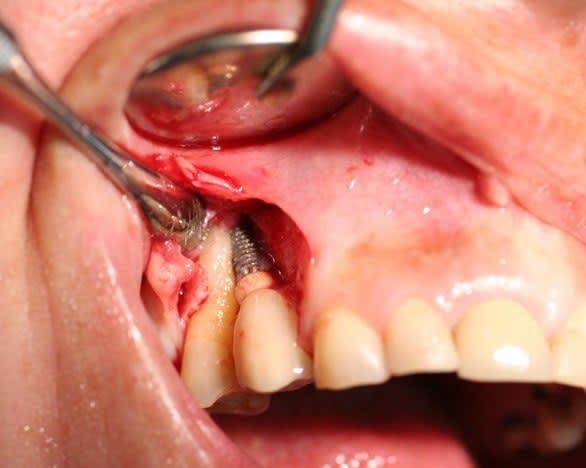

Mais un patient est arrive au cabinet avec 7 Implants maxillaires et rien de plus, bilan des courses , 2 mobiles, 2 avec l'hexagone externe cassé, 1 avec la vis prothétique cassée dans l'implant. Il reste un en place de 17 a moitie enterré et l'autre en 16, ni l'un i l'autre ont une vis de couverture ou un piler de cicatrisation.

P.S : Pour le fun le cas pour lequel , je suis énervé et celui du proces est pire mais je ne peux pas le publier.

Il a laissé la patiente 5 mois comme ça en disant que tout allait bien, l'endo je l'ai faite moi au cas ou !!

Le second va être virer aussi car il est intra-sinusien générant une sinusite chronique.